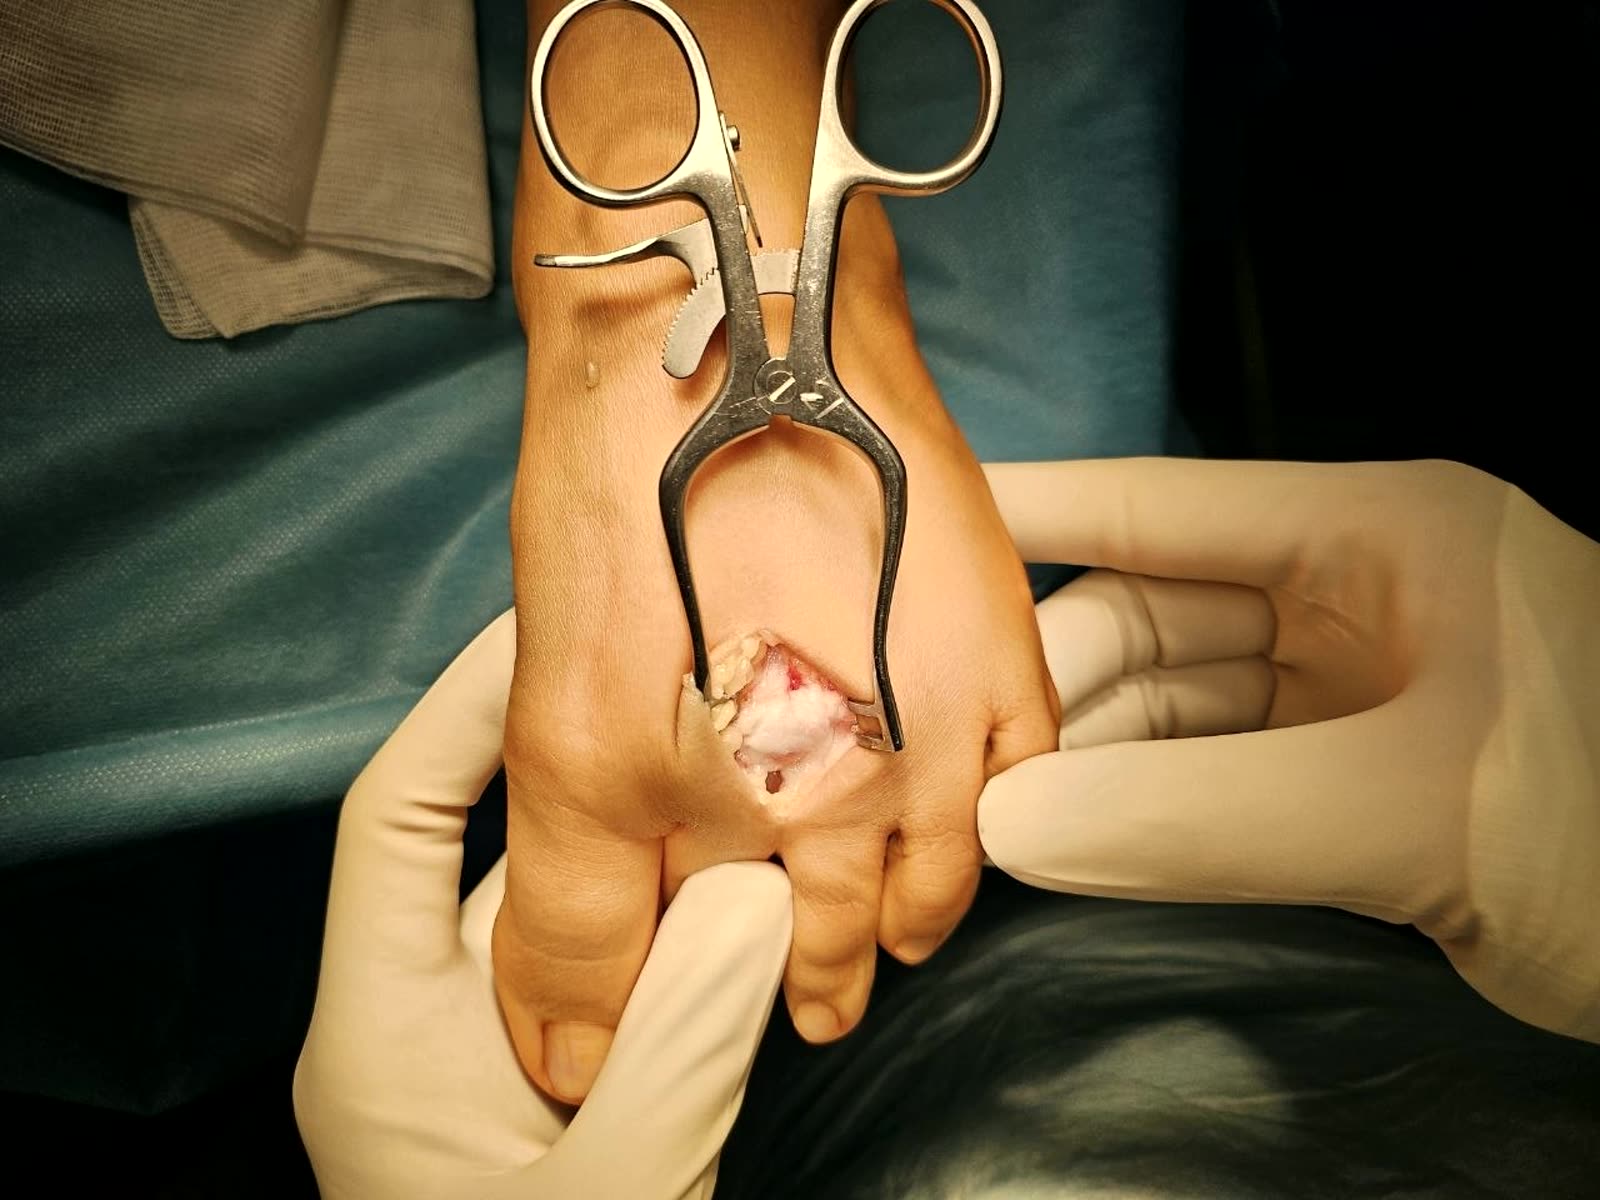

Репозиция

Репозиция синдесмоза обычно выполняется с помощью репозиционных щипцов (bone clamp). Однако многочисленные исследования показали, что положение щипцов или винта может вызывать подвывих. Установка щипцов в нейтральном положении перпендикулярно синдесмозу сопровождается меньшим числом подвывихов по сравнению с косым положением. Прямая визуализация синдесмоза рекомендуется во всех случаях для минимизации риска подвывиха.